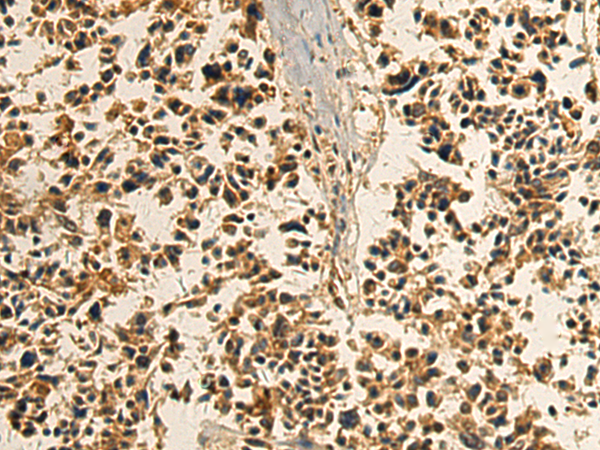

分类: 科研抗体货号: P07384别名: EDF; FRP应用: WB,IHC反应种属: Human, Mouse, Rat